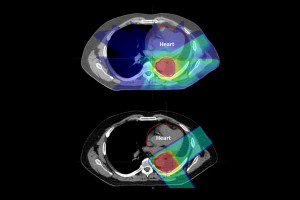

Protons are relatively heavy, positively charged particles that hit their target and stop.

X-ray beams consist of photons, which are much smaller particles that have almost no mass, allowing them to travel all the way through the body, passing through healthy tissue on the way out.